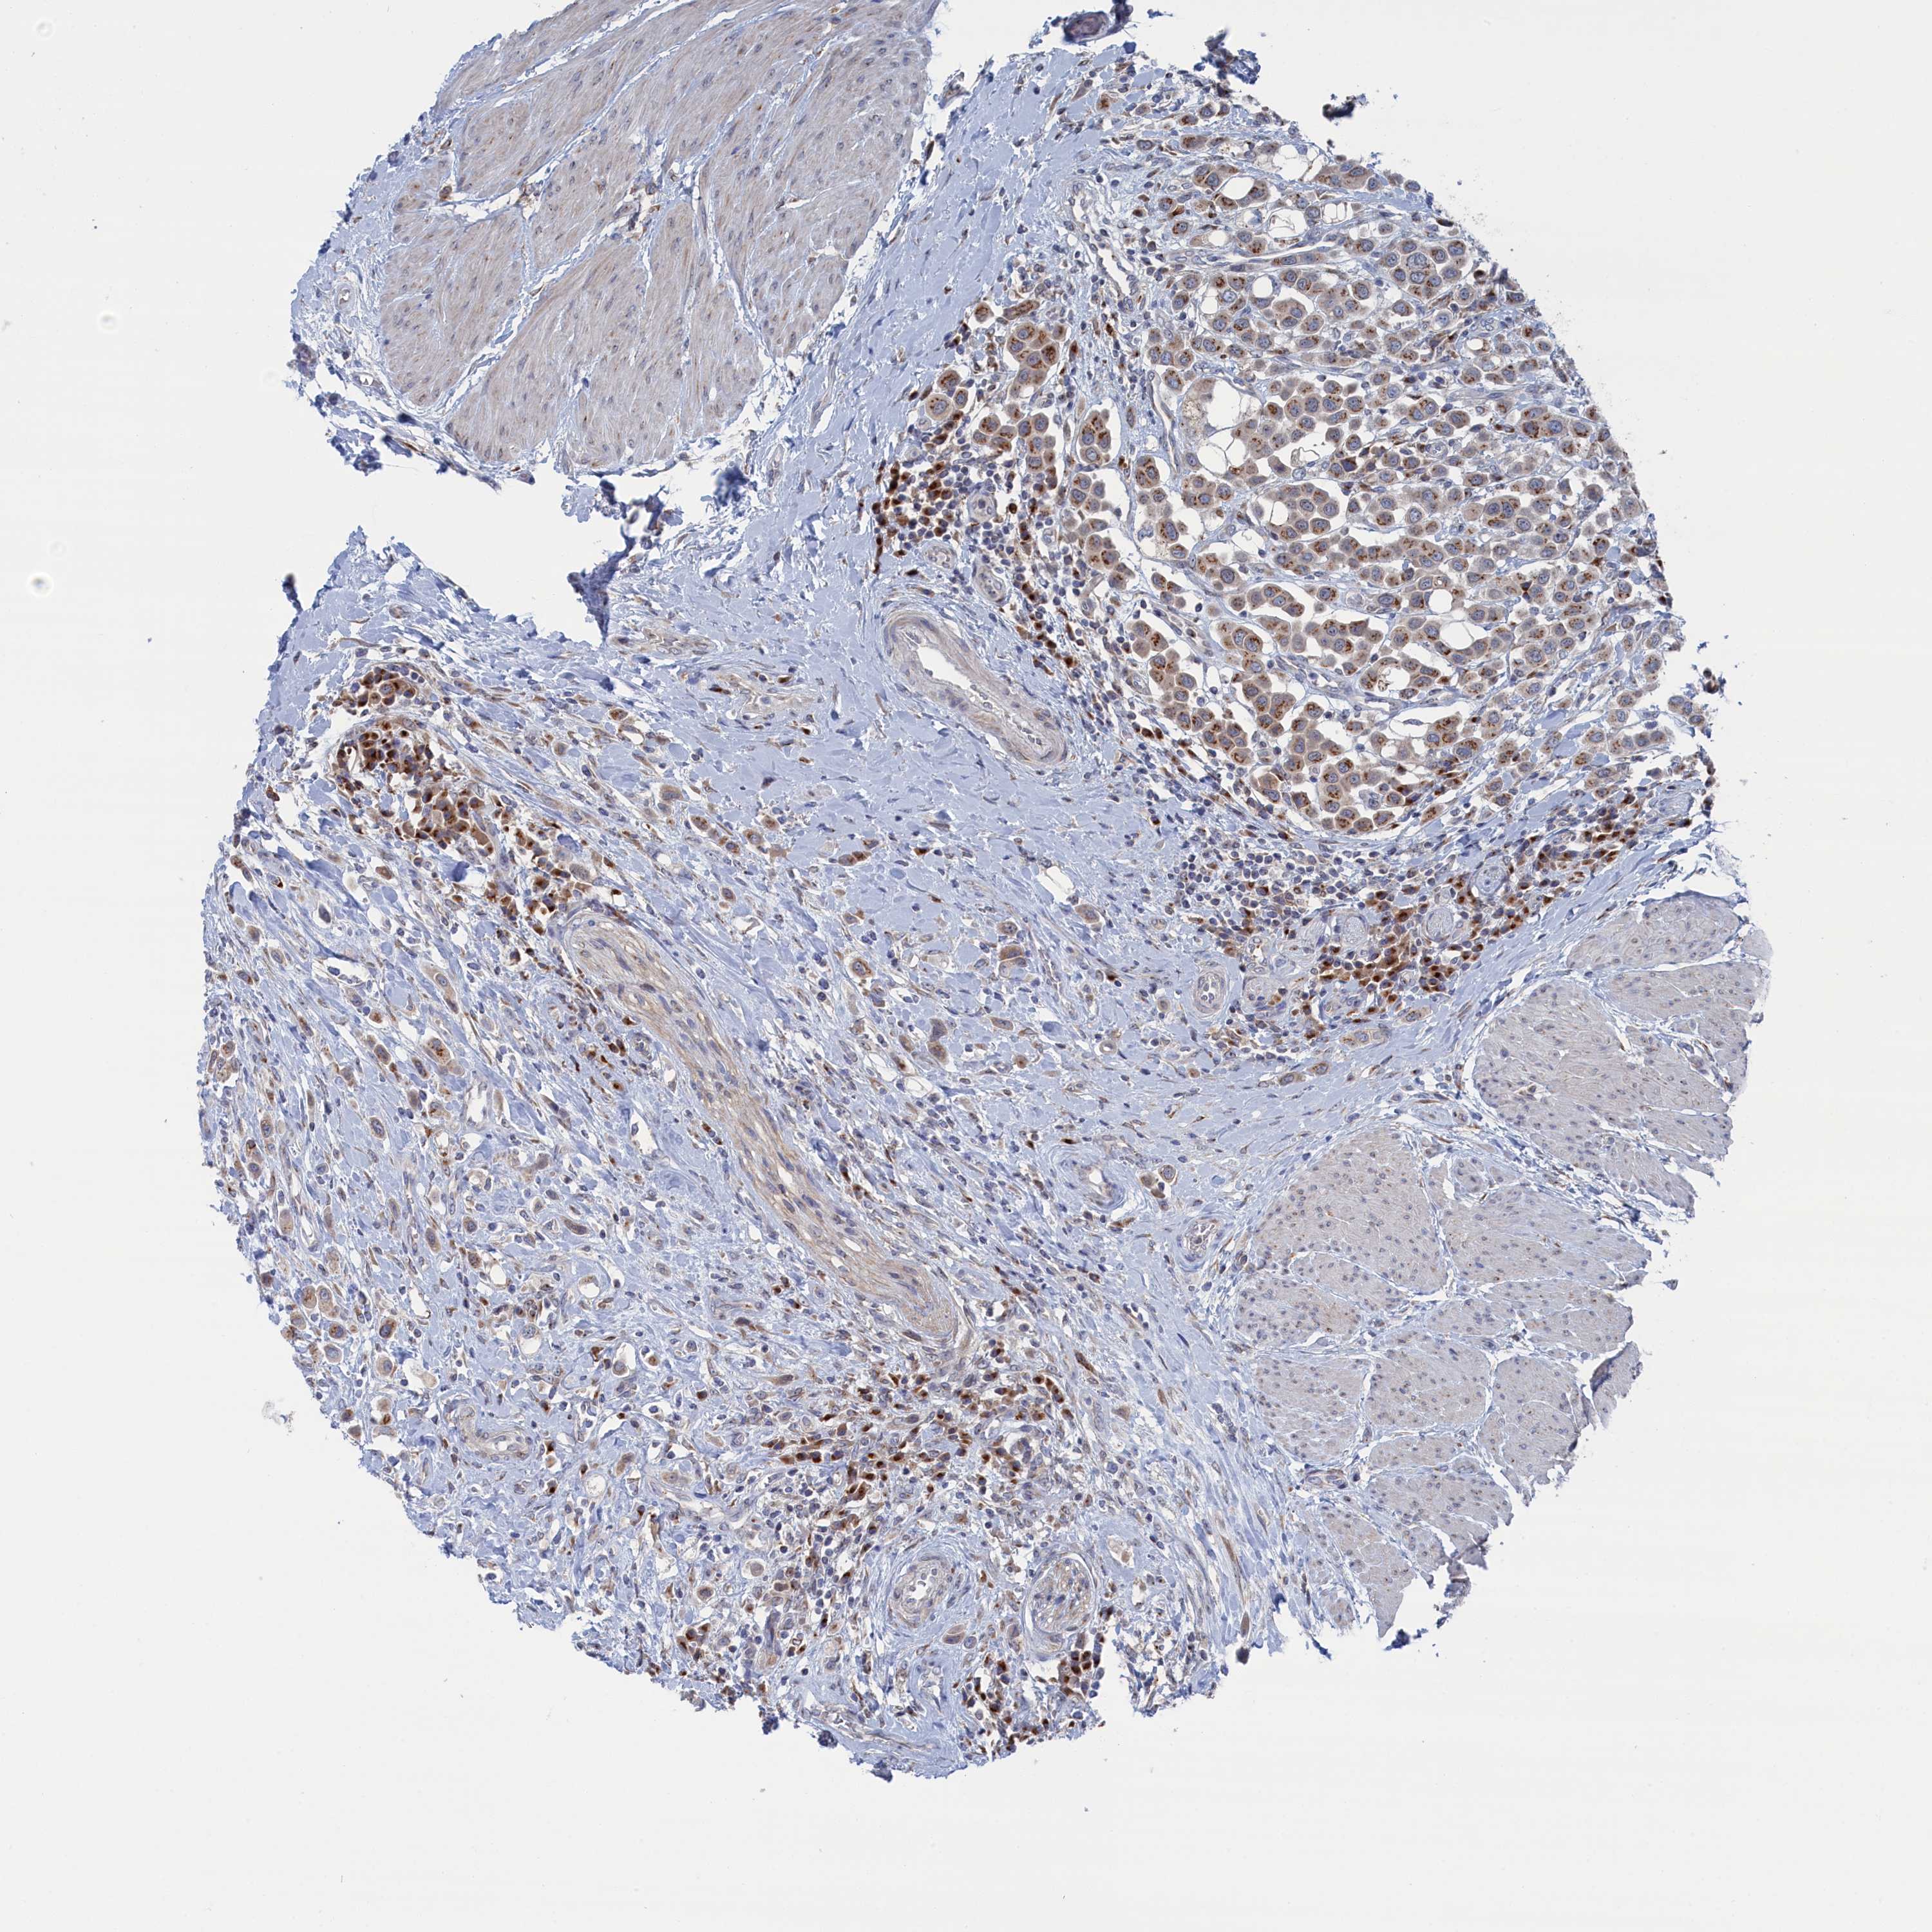

UROTHELIAL CANCER - Protein expressioni

A mouse-over function shows sample information and annotation data. Click on an image to view it in a full screen mode. Samples can be filtered based on level of antibody staining by selecting one or several of the following categories: high, medium, low and not detected. The assay and annotation is described here.

Note that samples used for immunohistochemistry by the Human Protein Atlas do not correspond to samples in the TCGA dataset.

Antibody stainingi

Antibody staining in the annotated cell types in the current human tissue is reported as not detected, low, medium, or high, based on conventional immunohistochemistry profiling in selected tissues. This score is based on the combination of the staining intensity and fraction of stained cells.

Each image is clickable and will lead to virtual microscopy that enables deeper exploration of all samples and also displays staining intensity scores, fraction scores and subcellular localization as well as patient and tissue information for each sample.

Antibody HPA043160

Staining

High

Medium

Low

Not detected

Intensity

Strong

Moderate

Weak

Negative

Quantity

>75%

75%-25%

<25%

None

Location

Nuclear

Cytoplasmic/membranous

Cytoplasmic/membranous,nuclear

Urothelial carcinoma, Low grade